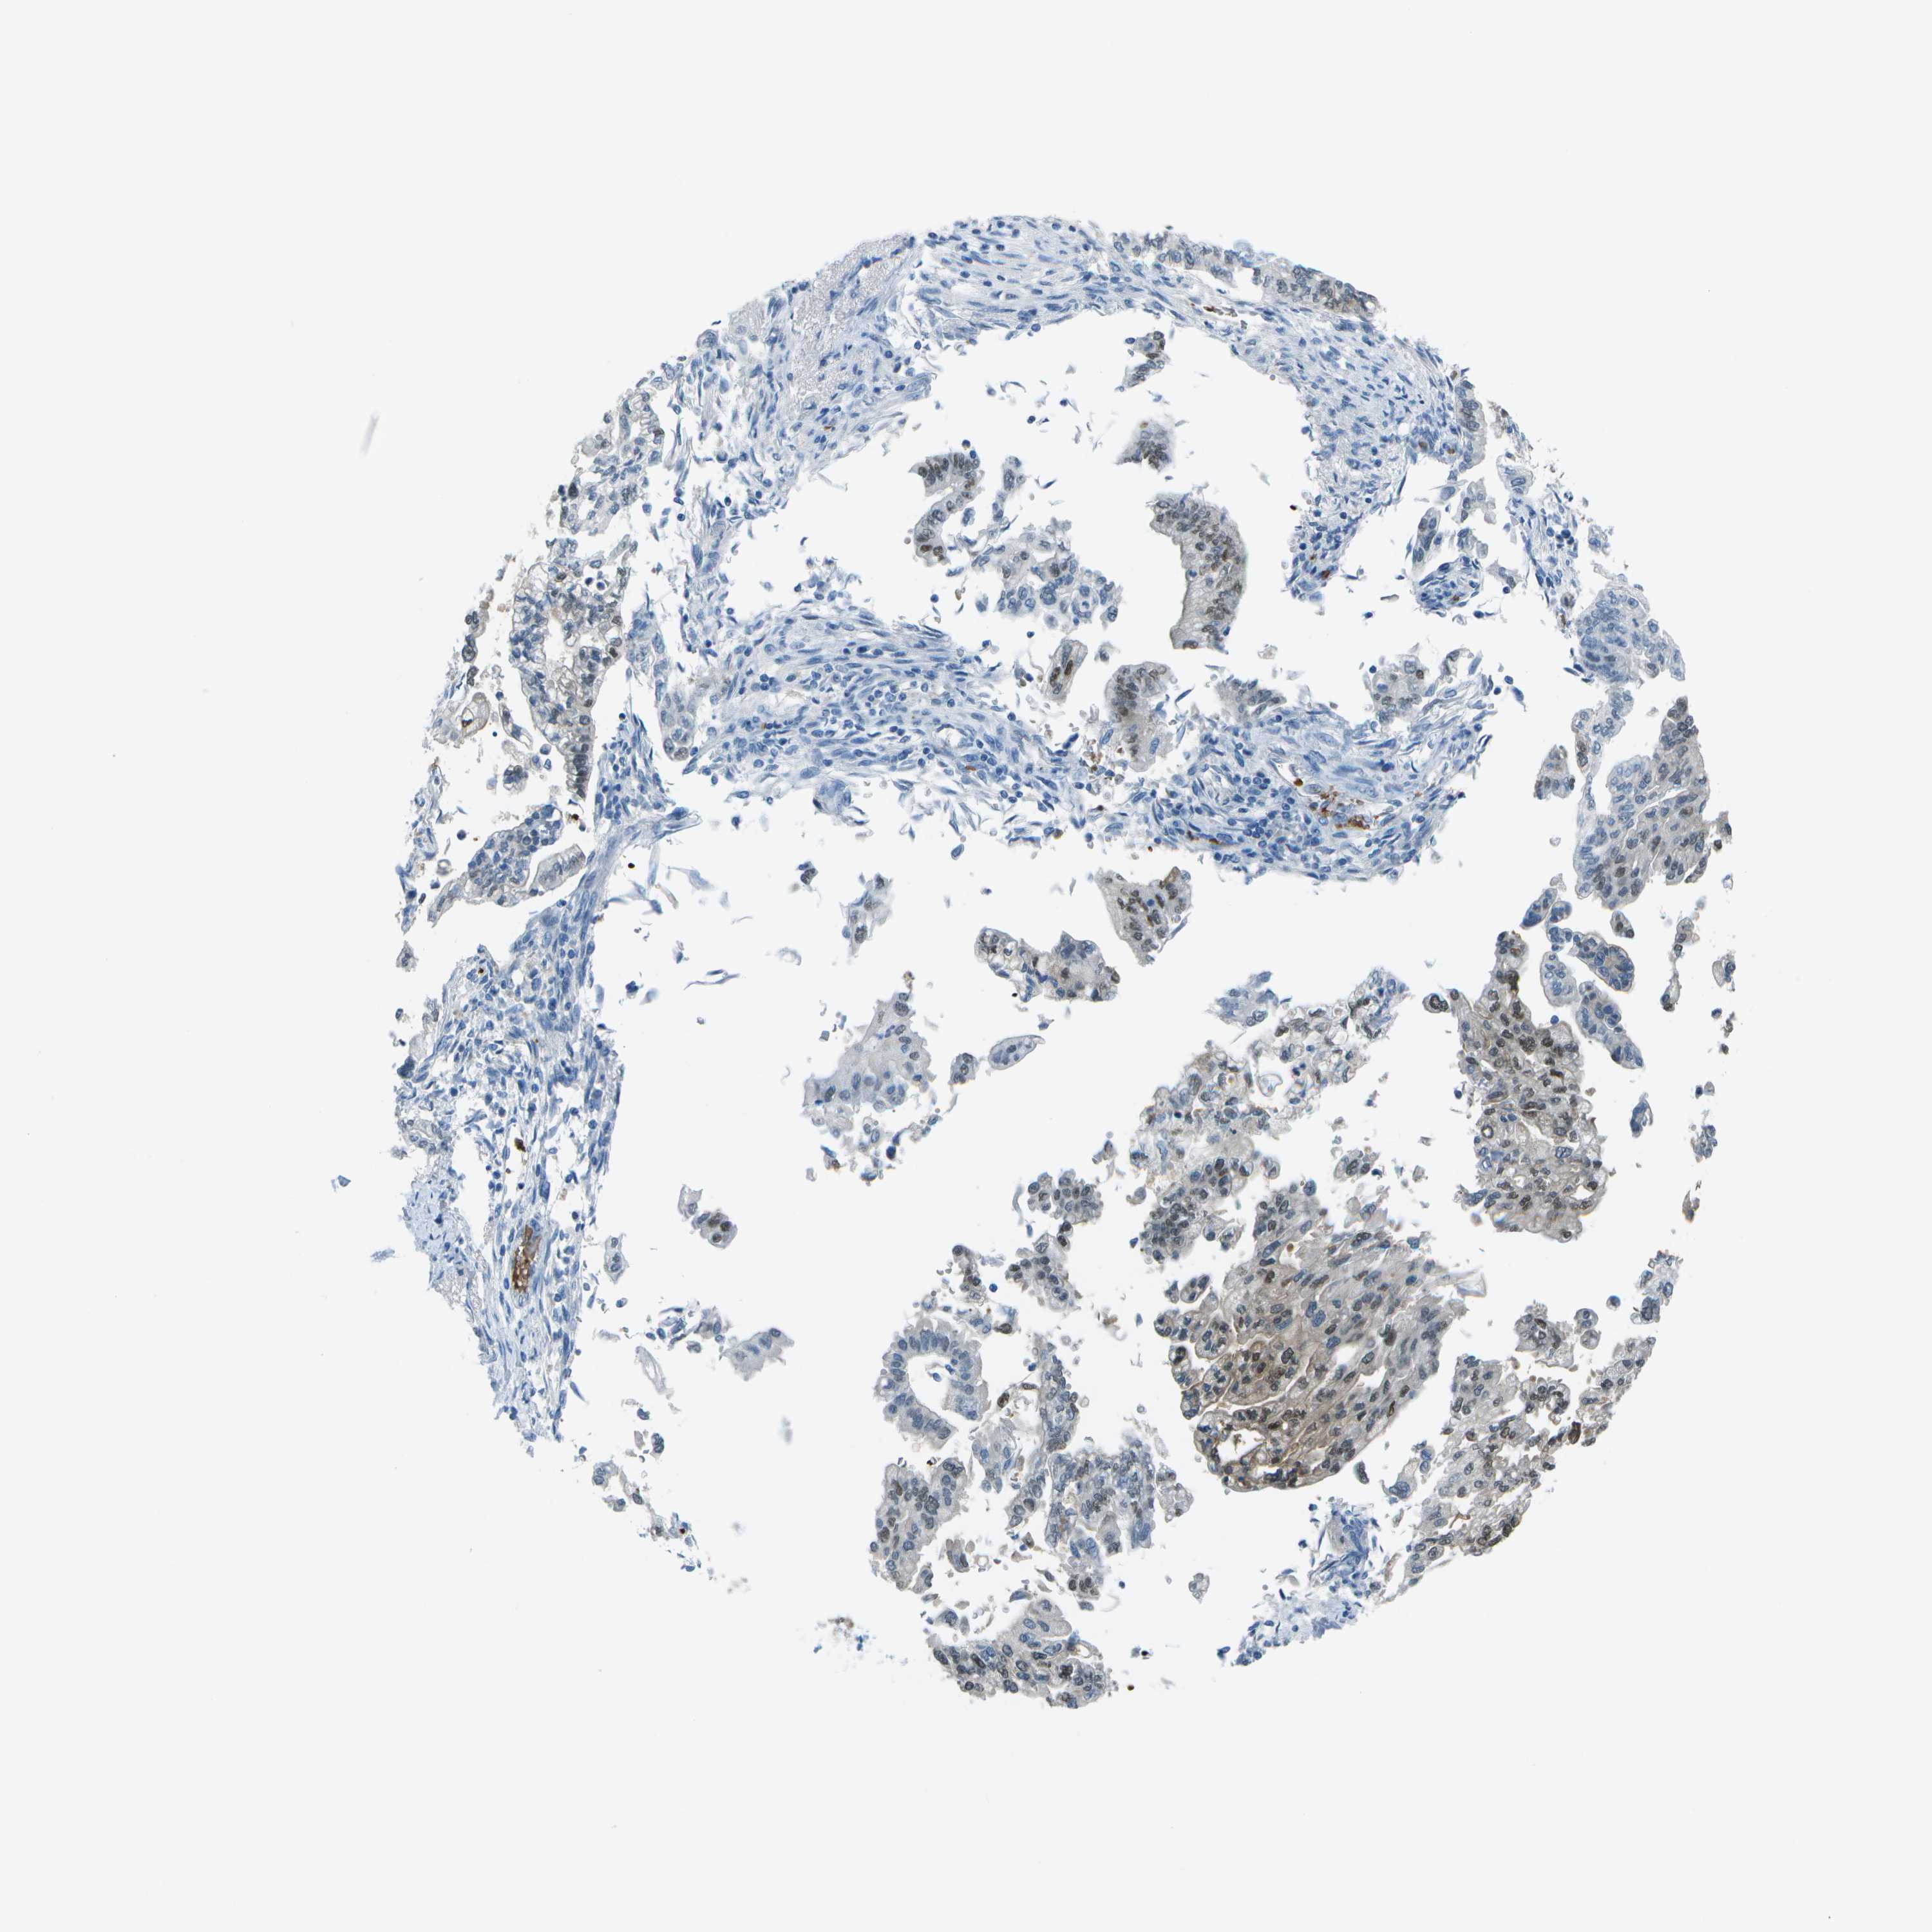

PANCREATIC CANCER - Protein expressioni

A mouse-over function shows sample information and annotation data. Click on an image to view it in a full screen mode. Samples can be filtered based on level of antibody staining by selecting one or several of the following categories: high, medium, low and not detected. The assay and annotation is described here.

Note that samples used for immunohistochemistry by the Human Protein Atlas do not correspond to samples in the TCGA dataset.

Antibody stainingi

Antibody staining in the annotated cell types in the current human tissue is reported as not detected, low, medium, or high, based on conventional immunohistochemistry profiling in selected tissues. This score is based on the combination of the staining intensity and fraction of stained cells.

Each image is clickable and will lead to virtual microscopy that enables deeper exploration of all samples and also displays staining intensity scores, fraction scores and subcellular localization as well as patient and tissue information for each sample.

Antibody HPA016646

Antibody CAB003696

Staining

High

Medium

Low

Not detected

Intensity

Strong

Moderate

Weak

Negative

Quantity

>75%

75%-25%

<25%

None

Location

Nuclear

Cytoplasmic/membranous

Cytoplasmic/membranous,nuclear

Adenocarcinoma, NOS

Adenocarcinoma, metastatic, NOS